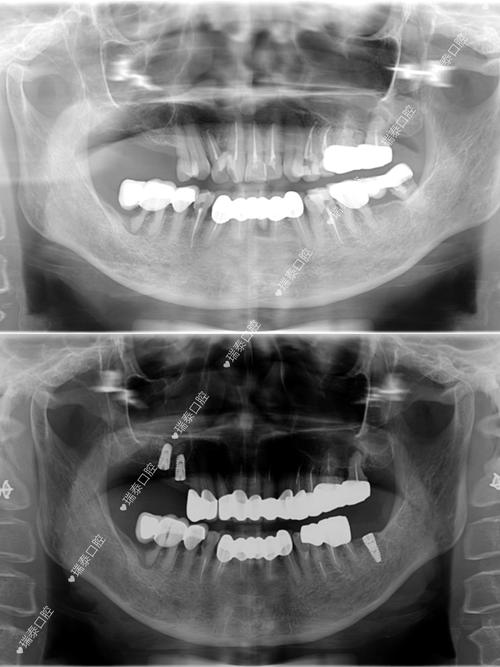

- 术前咨询与检查: 预约种植医生面诊,医生会进行口腔检查(视诊、触诊、叩诊等),拍摄口腔全景片(曲面断层片)和CBCT(锥形束CT),评估牙槽骨的骨量、密度、位置,以及邻牙、重要解剖结构(如下牙槽神经管、上颌窦)的关系,同时检查全身健康状况(如血糖、血压、凝血功能等是否适合手术)。